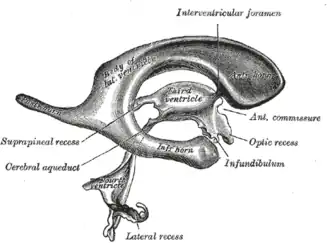

Drawing of a cast of the ventricular cavities, viewed from the side; oriented facing right. | |

Each lateral ventricle resembles a C-shaped cavity that begins at an inferior horn in the temporal lobe, travels through a body in the parietal lobe and frontal lobe, and ultimately terminates at the interventricular foramina where each lateral ventricle connects to the single, central third ventricle. Along the path, a posterior horn extends backward into the occipital lobe, and an anterior horn extends farther into the frontal lobe.[1]

Structure

Each lateral ventricle takes the form of an elongated curve, with an additional anterior-facing continuation emerging inferiorly from a point near the posterior end of the curve; the junction is known as the trigone of the lateral ventricle. The centre of the superior curve is referred to as the body, while the three remaining portions are known as horns (cornua in Latin); they are usually referred to by their position relative to the body (anterior, posterior, or inferior), or sometimes by the lobe of the cerebral cortex into which they extend. Though somewhat flat, the lateral ventricles have a vaguely triangular cross-section. Ependyma, which are neuroepithelial cells, line the ventricular system including the lateral ventricles.[1][2]

Anterior horns of the lateral ventricle

Body of the lateral ventricle

Trigone of the lateral ventricle

Posterior horn of the lateral ventricle

Inferior horn of the lateral ventricle